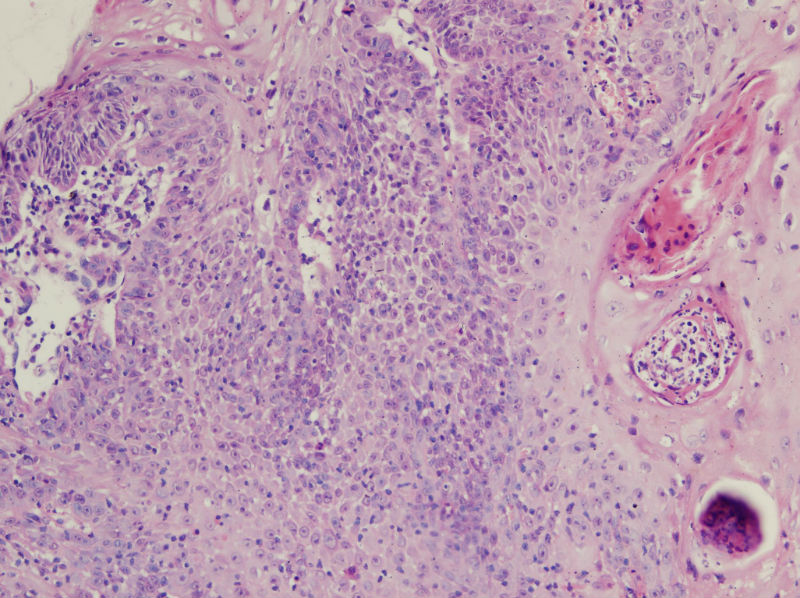

男,45岁,上唇菜花样肿物,请老师指教

高分化鳞癌

倾向于鳞癌,恶黑不除外。